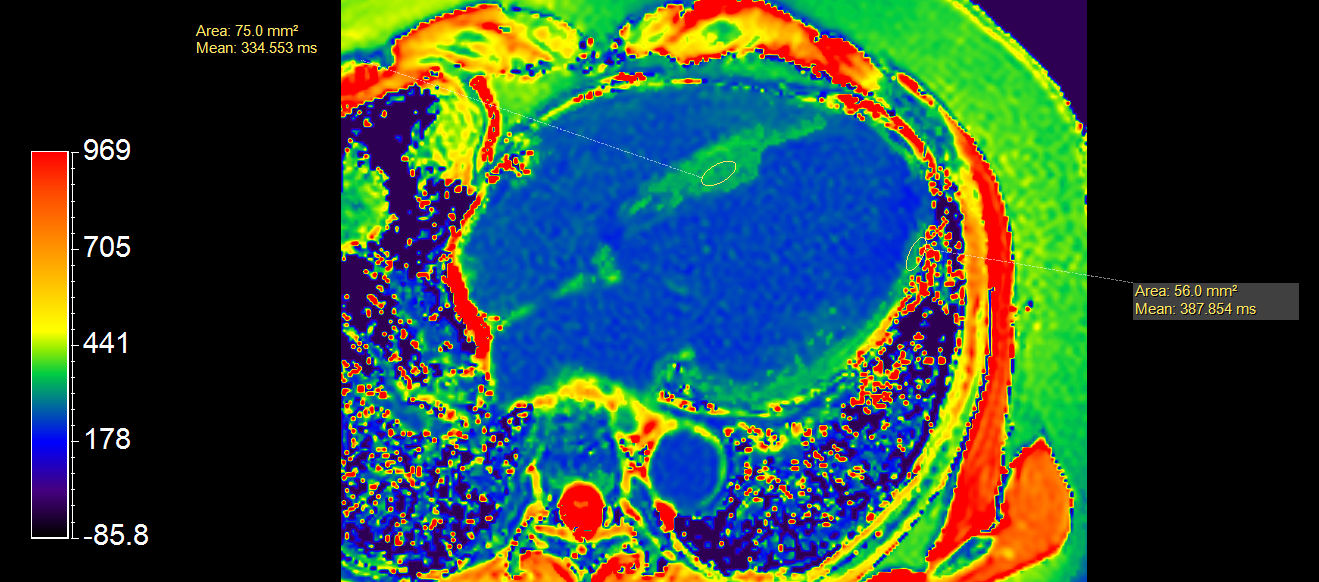

Short axis view T1 Map (enhanced)